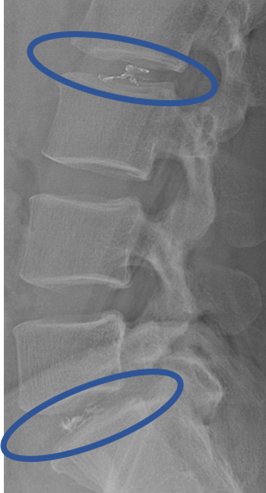

画像及び所見について

L1/2: 異常なし

L2/3: 異常なし ※初期の兆候あり、本人希望により治療決定

L3/4: 異常なし

L4/5: 異常なし

L5/S: 変性、膨隆、左椎間孔狭窄

以上の事が画像上認められます。

L2/3、5/S に

変性、膨隆、左椎間孔狭窄 を認め、主症状の原因の可能性が高い。